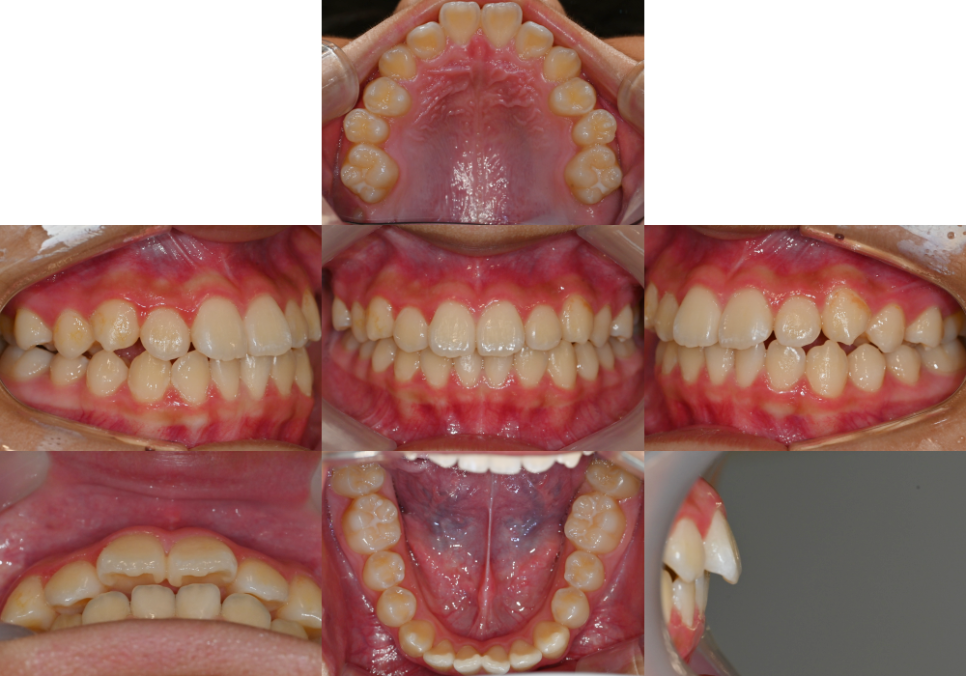

| 1. 총생이란 무엇인가요?

23.08.17

총생은 이가 들어설 공간이 부족해서

이들이 겹치거나 비틀어진 상태를 말하는데요.

많은 분들이

단순히 ‘치아가 삐뚤어졌다’고만

생각하시지만, 실제로는

훨씬 복잡한 문제로,

가장 큰 문제점으로는

위아래 어금니가 제대로 맞물리지 않는

부정교합이 발생한다는 점입니다.

정상적인 교합에서는

위아랫니가 정확히 맞물려야 되는데,

총생이 있으면 이러한 기능적 교합이 어려워집니다.

| 3. 발치 없이도 교정이 가능한가요?

다행히 심한 골격적 문제나 심각한 총생이 아니라면

발치 없이도 치열 개선이 가능합니다.